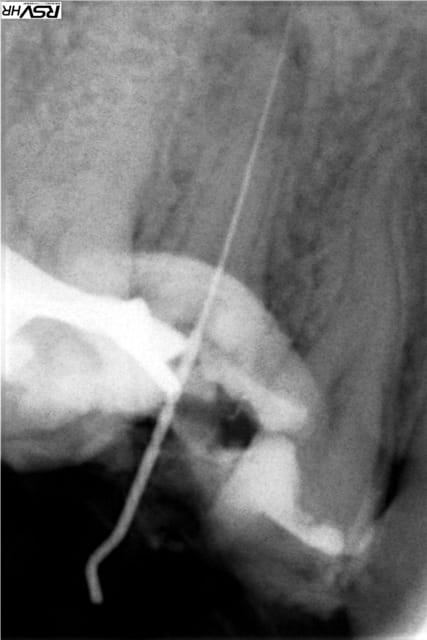

la même chose, avec même des instruments fracturés :)

Vw campersurfvan bmnk1q - Eugenol